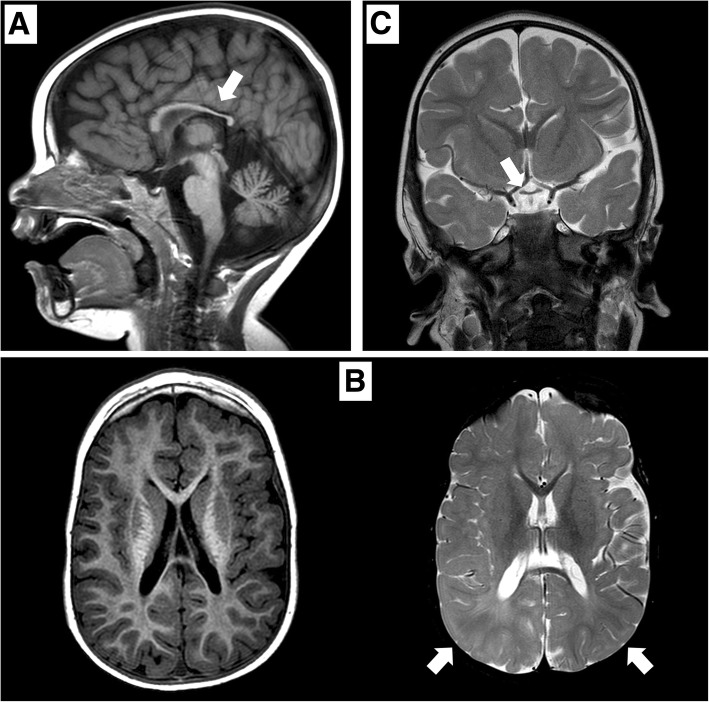

矢状位 T1 加权图像显示胼胝体发育不全(白色箭头)。 b 轴向 T1 加权(左)和轴向 T2 加权(右)图像显示胼胝体发育不全和双侧皮层下顶叶白质(白色箭头)中改变的、不明确的信号。 c 显示视交叉发育不全的冠状 T2 加权图像(白色箭头)

德莫塞尔综合征基因解码

在 2 岁时,患者无法保持目光接触,也没有发展语言技能。 直到 3 岁时,他才能独立坐下。此时,头颅 MRI 显示双侧视神经发育不全,并证实胼胝体发育不全(图 (图 1).1)。 为评估先天性心脏缺陷而进行的超声心动图显示无阻塞的室间隔肥大。